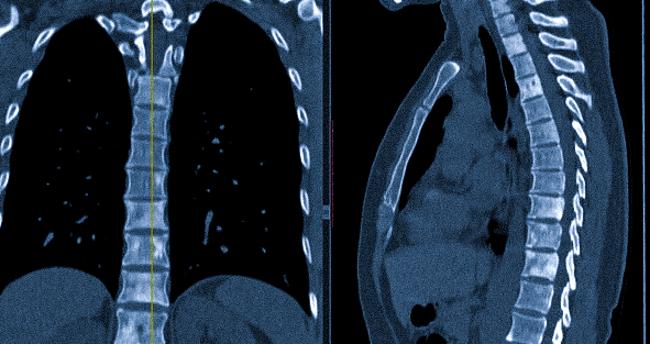

КТ головы, шеи и органов грудной клетки показала: разрушение кортикальной пластинки правой лобной кости и множественные метастатические изменения в обоих легких и лимфатических узлах области средостения. Для детального исследования распространенности метастазов в костной системе была рекомендована остеосцинтиграфия с использованием остеотропного радиофармпрепарата (РФП).

Компьютерная томография выявляет области разрушения костных и хрящевых элементов, а также переломы и трещины в телах и отростках. При нарушении формы позвоночного канала может произойти сжатие спинного мозга и повреждение нервной ткани.

КТ наглядно демонстрирует патологические изменения, позволяет установить характер поражений и степень вовлечения окружающих структур.

Компьютерная томография позволяет уточнить диагноз, определить локализацию и размеры патологического очага, составить план лучевой терапии злокачественной опухоли. Перед хирургическим вмешательством КТ помогает оценить объем и характер предстоящей операции.

Внешний вид метастазов на компьютерной томографии напрямую зависит от уровня минерализации опухолевых тканей. Существует три типа очагов метастазирования в костях:

Остеолитические метастазы приводят к уменьшению высоты позвонка. Вторичное поражение происходит с активацией клеток, которые растворяют костную ткань. Литические процессы вызывают уменьшение плотности, структурные нарушения, а также образование гиподенсных участков на КТ-снимках.